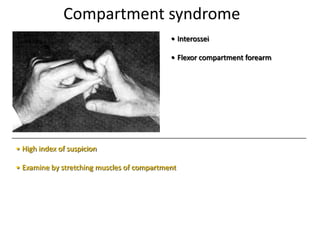

- Conditions that require emergency referral are discussed, such as bleeding, amputation, replantation, compartment syndrome, infections, and high pressure injection injuries. Proper management of these conditions focuses on rapid assessment and treatment to prevent further tissue damage.